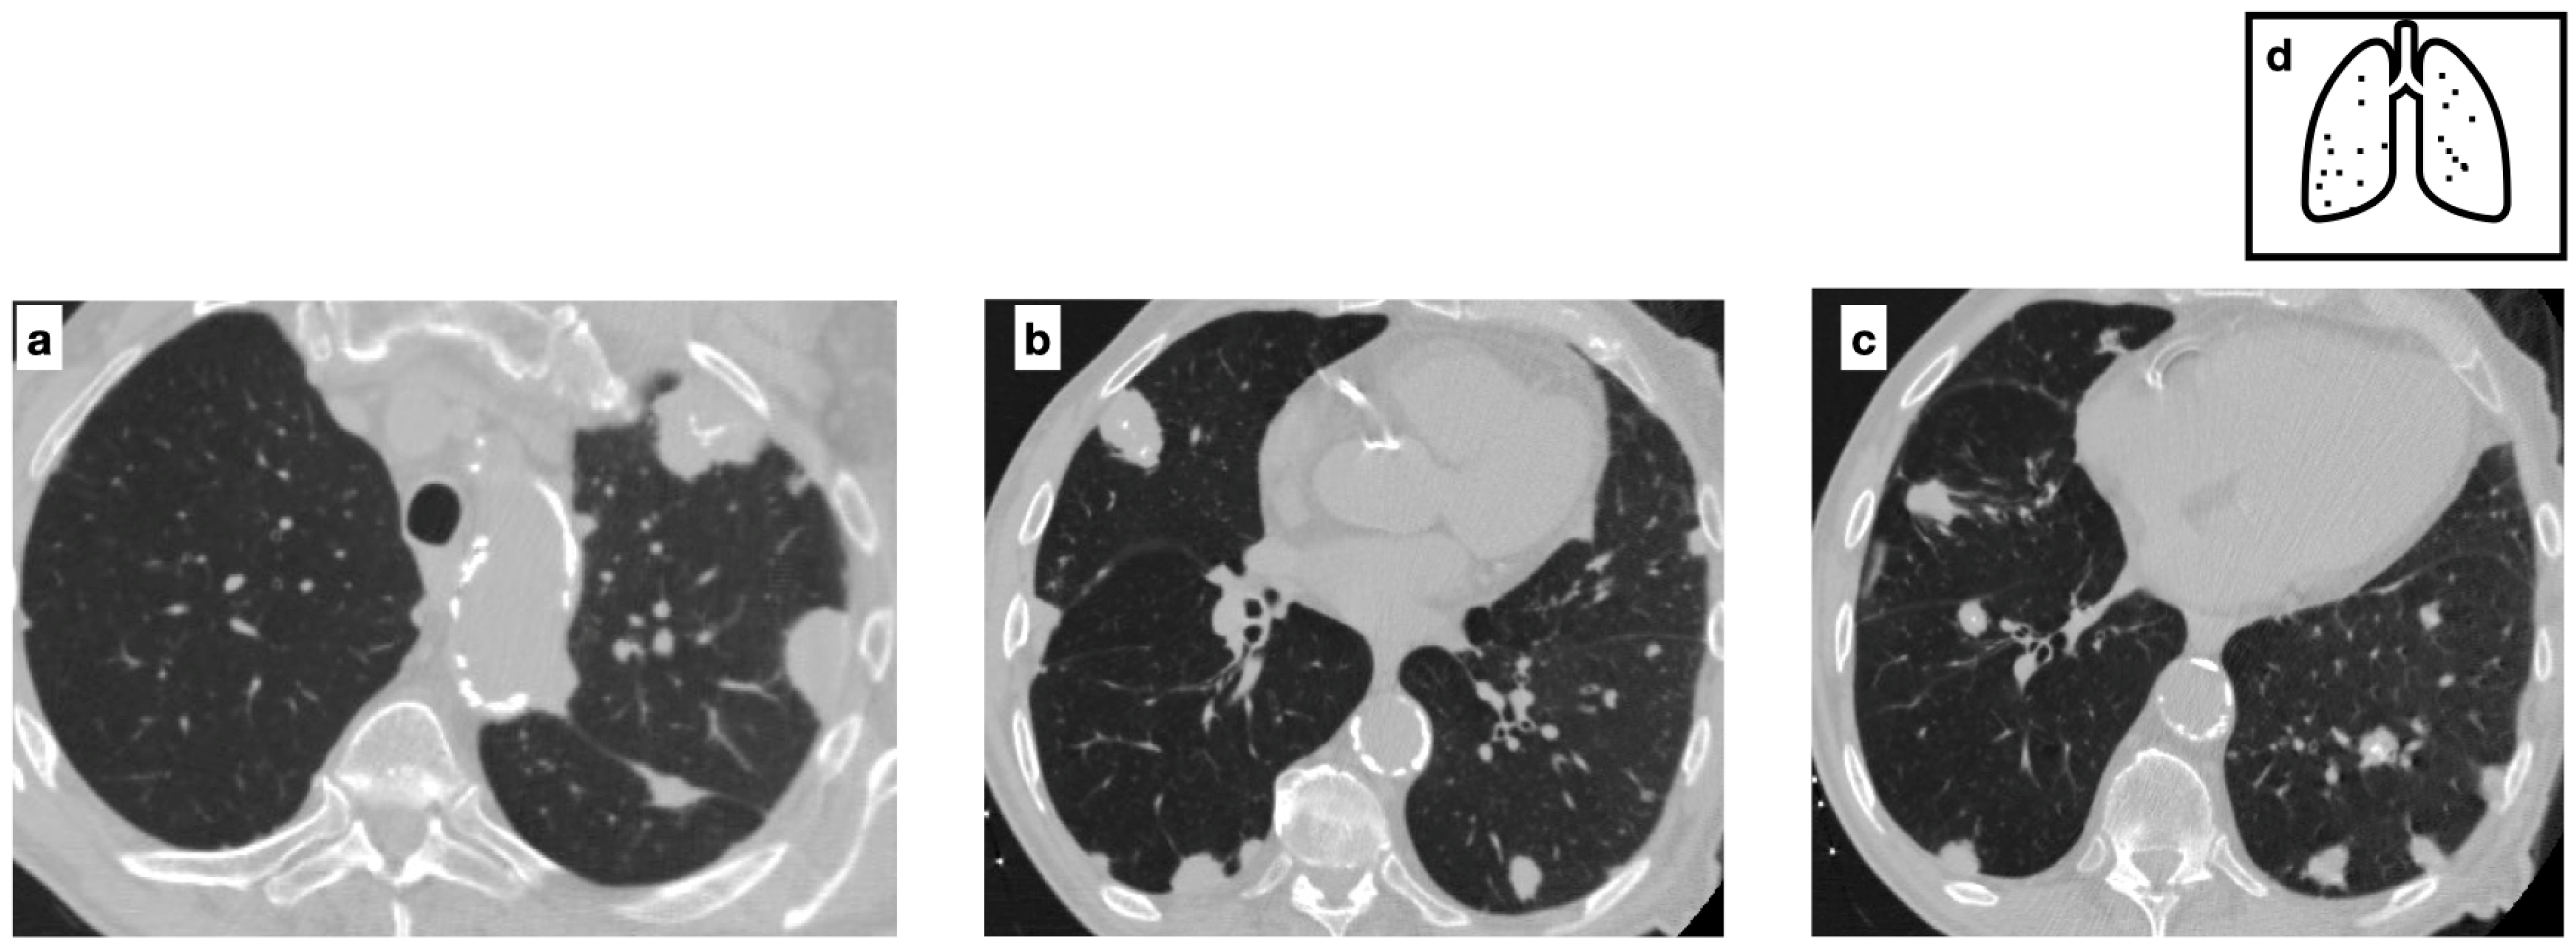

Multifocal pulmonary nodules, variable in size, with smooth and lobulated contours, some of which are characterized by central calcification in a patient with biopsy-proven amyloidosis (a–c). The nodular parenchymal amyloidosis is commonly characterized by discrete nodules, heterogeneous in size, with subpleural predominance. Pattern of calcification (d).

Pulmonary manifestations of amyloidosis involve two distinct patterns of lung parenchymal involvement. The nodular parenchymal type is the most common and is typically associated with localized AL amyloidosis. It is commonly characterized by discrete nodules, which may be single or multiple, heterogeneous in size, with smooth or lobulated margins and a subpleural predominance. Calcifications are present in approximately 50% of cases, often exhibiting a central or punctate pattern (Figure 7). While nodular cavitation is rare, lesions may slightly increase in size and number over time. Histopathologic confirmation is essential for a definitive diagnosis [23].

Figure 7.